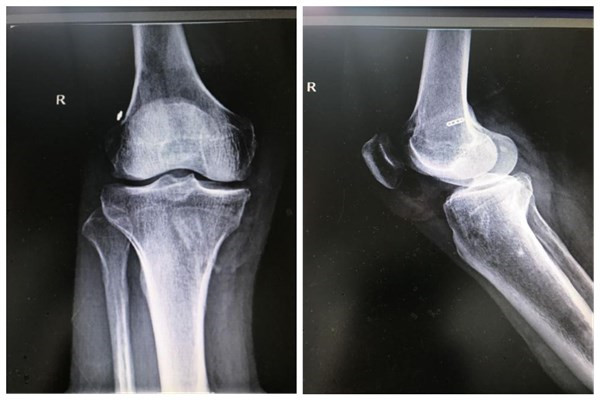

47岁女性,患者右膝前交叉韧带重建术后照片

10月1日当天,正是国庆长假第一天,骨科一病区罗三彤副主任医师、黄晓梦护士长,带着对患者的关怀来到了石碑坪镇,去探望三位术后患者,一例是47岁女性患者,去年因扭伤右膝关节,到我院诊断是右膝前交叉韧带断裂,并行前右膝交叉韧带重建术,术后康复出院。今日对患者回访,检查右膝关节稳定性良好,下蹲、行走、跑步患者恢复良好!